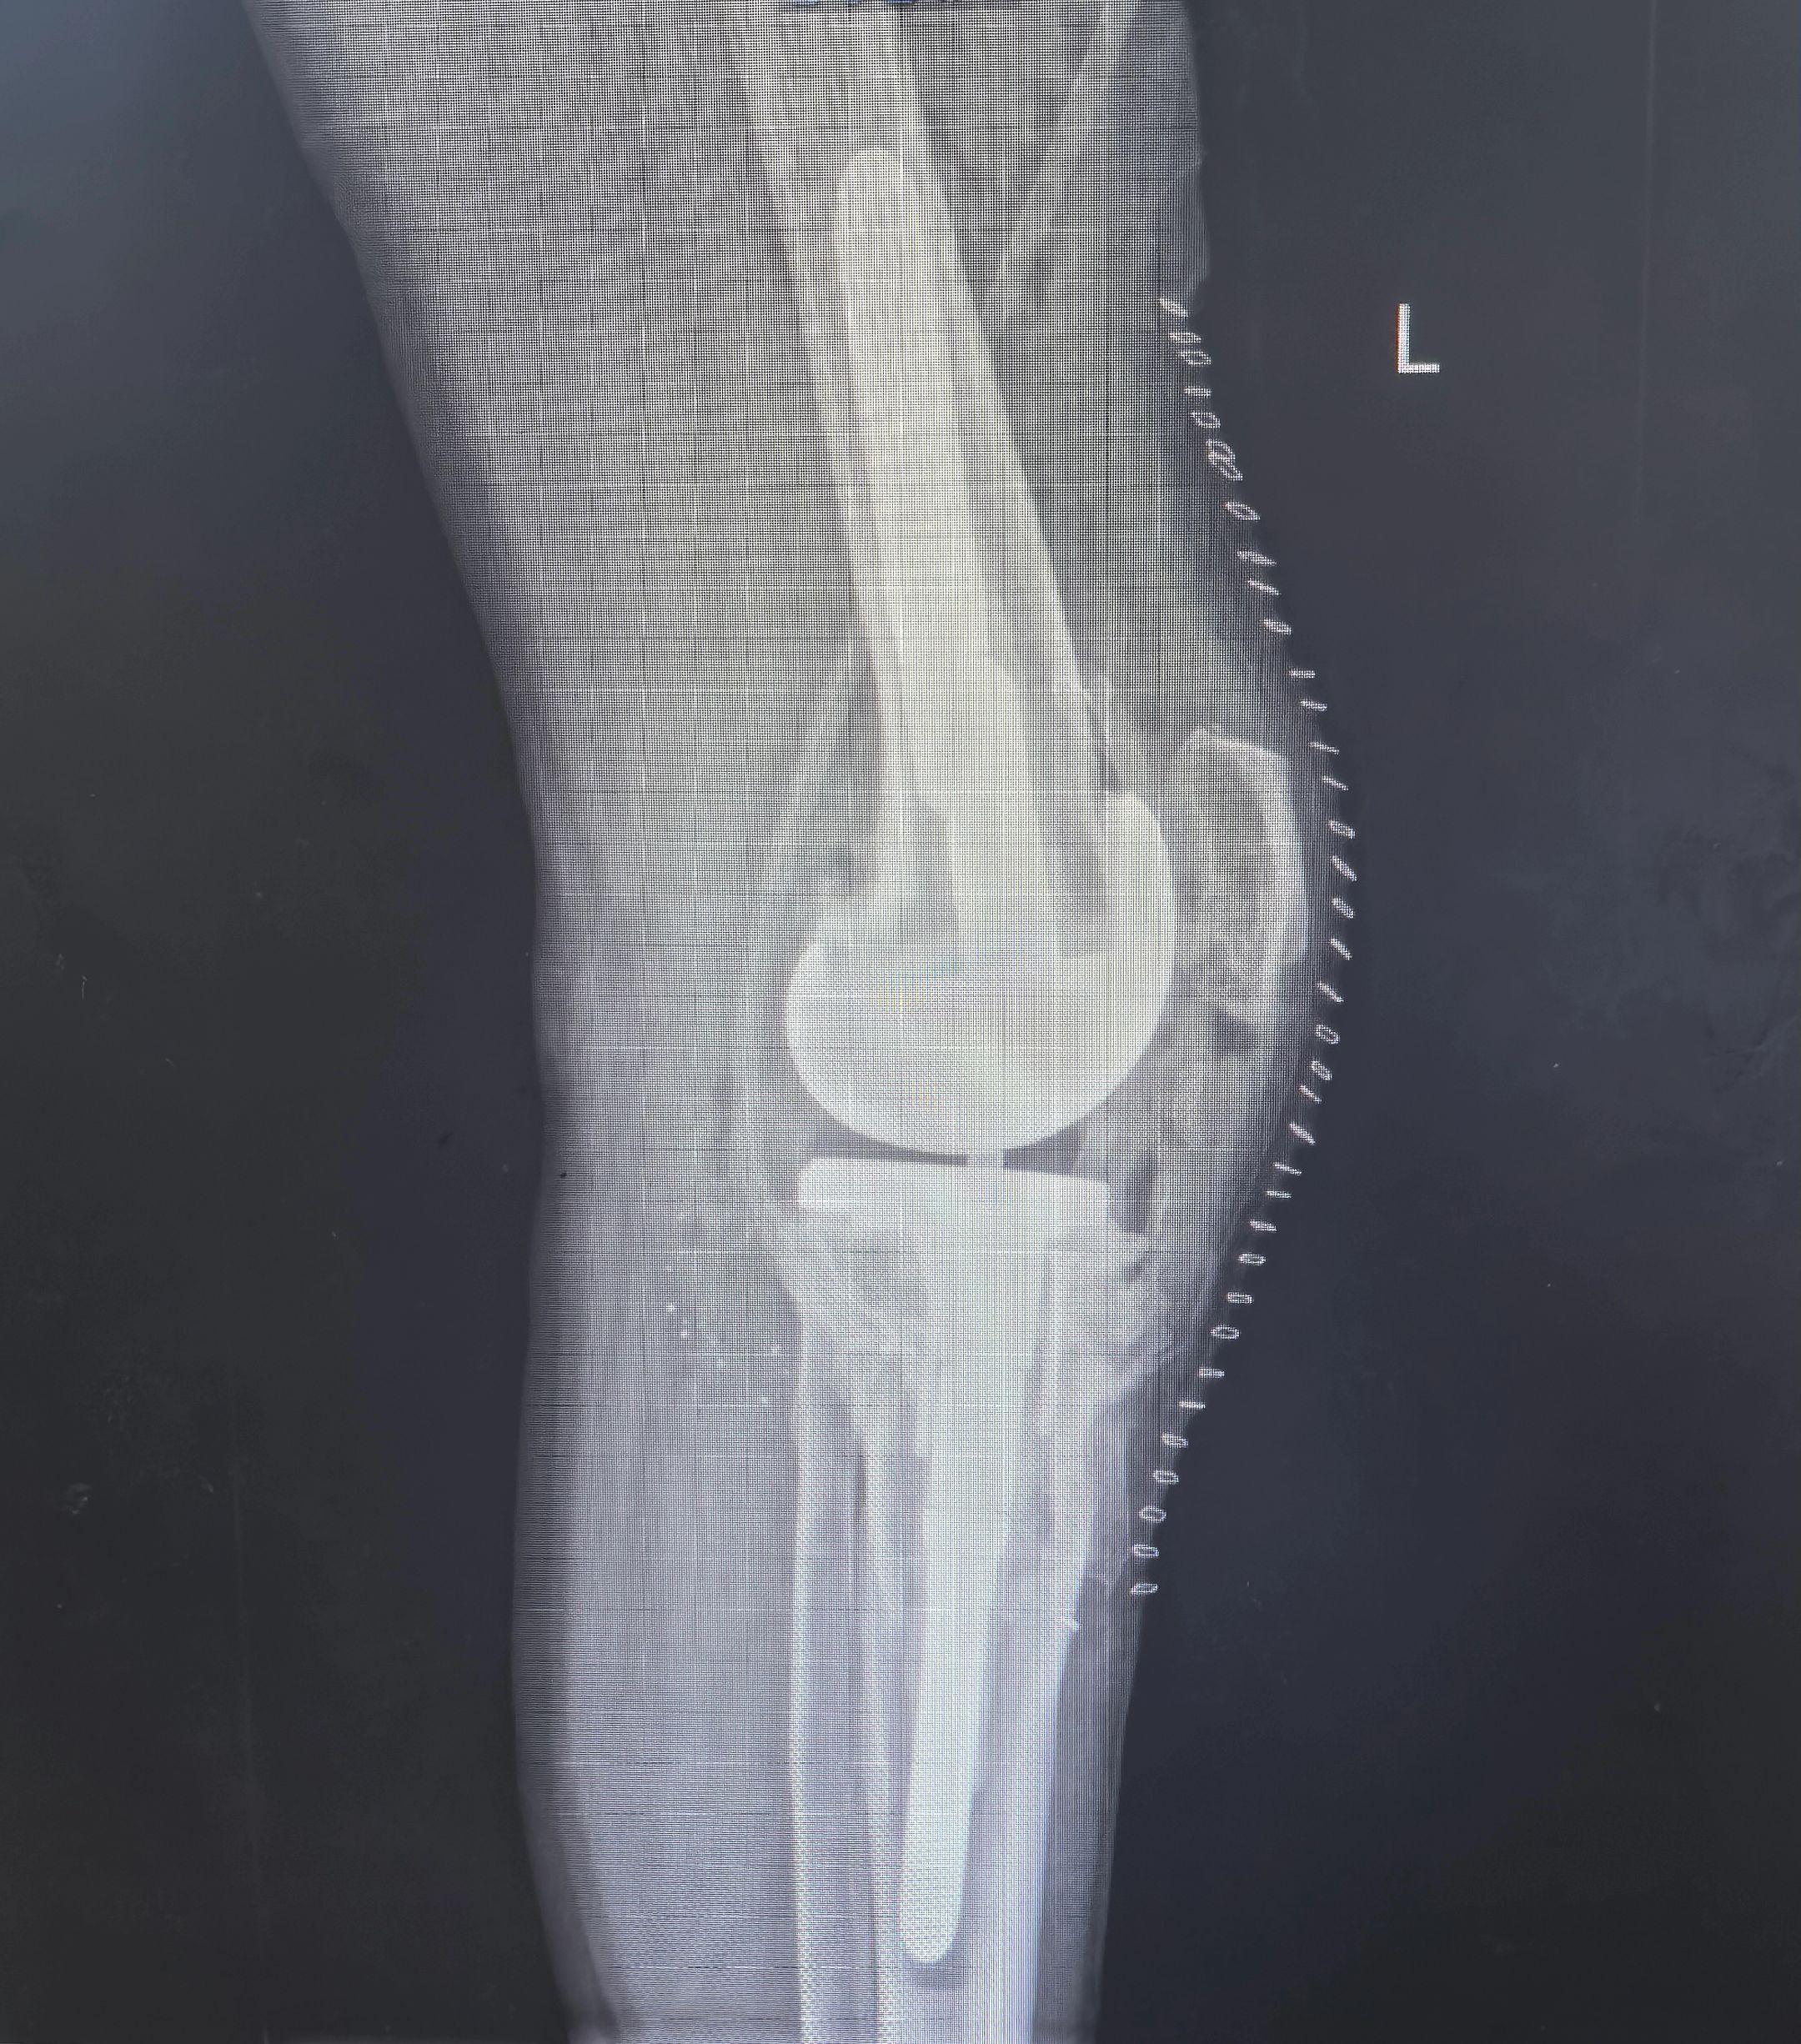

骨关节炎,膝关节置换。(这几天一忙忘了,接上一条)术后第二天晨查房,看到病人合不拢嘴,觉得所有的努力和付出都值得了!几个地方都建议直接铰链膝,这次备了cck和铰链膝,最终视术中情况选择了cck,对患者是个最有利的决策。愿所有的患者都能早日恢复正常生活🌹